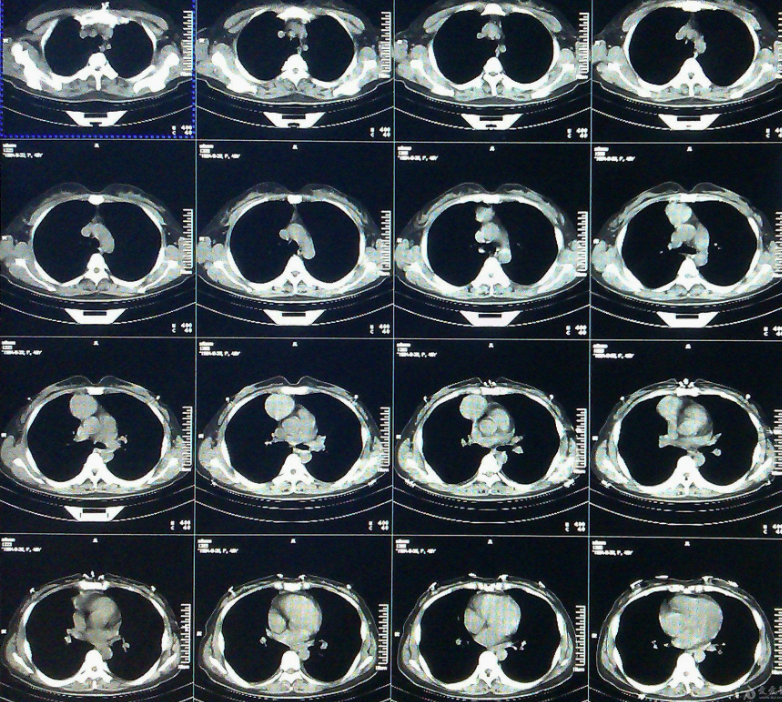

平掃CT發現左上肺葉尖后段有15cm結節影,結合病史考慮是轉移北人胸外王主任,北醫胸外李主任第二天閱片會診,周教授仔細;三住院手續辦理要求一北醫六院北院區要求以8月17日通知為例必備材料患者本人到場

平掃CT發現左上肺葉尖后段有15cm結節影,結合病史考慮是轉移 北人胸外王主任,北醫胸外李主任第二天閱片會診,周教授仔細;三住院手續辦理要求一北醫六院北院區要求以8月17日通知為例必備材料患者本人到場患者本人身份證可查詢健康寶和行程碼的智能手機放射科提供的白色塑料袋內裝CT報告等影像資料抽血及核酸結果需用身份證打印CT報告通過白色塑料袋打印住院單標注為“最最最最重要”家屬要求同行家屬。

2018年6月CEA為56,7月復查升至7,9月切除3個腸息肉后,12月復查仍升至982019 2020年復查緩慢下降,2021年第一次復查降至38,完全走出困境事實上的好轉帶來最大助力,降到正常范圍給予莫大激勵期間進行了多次檢查,包括2次腸鏡2次胃鏡每年1次胸部CT每年2 3次血檢1次。